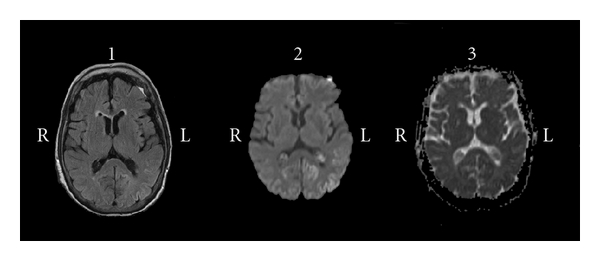

An 80-year-old female was admitted to the psychiatric unit for therapeutic adjustment. She had an unremarkable personal and family medical history. Her family referred hypothymia, occasional insomnia, and anxiety after the death of her only son, when she was 78, but she had never attended a psychiatric clinic till three months before admission. During that time she lived alone and took care of herself. At the first visit, she referred anxiety, anhedonia, loneliness, fatigue, and being afraid of living alone. She was diagnosed of adjustment disorder with depressed mood. Despite treatment with different antidepressants, the patient suffered clinical deterioration. At the next psychiatric consultation apathy, loosely structured guilty, hypochondriac, and nihilistic delusions were reported. In addition, she presented reduced speech output and psychomotor retardation with pseudocatatonic postures. At that moment, she was diagnosed of a major depressive episode with catatonia and psychiatric admission for therapeutic restructuring was agreed with her family. Despite different antidepressant and antipsychotic treatments, symptoms worsened and ECT was prescribed. The patient received eight bilateral ECT sessions during the following 25 days. During this period, the patient did not present any sign of improvement. In contrast, she progressively became disoriented, inattentive, perseverative, and her speech turned to be hypophonic, monotonous, with a paucity of content and difficulties in naming and understanding complex orders. She developed rigidity, postural tremor, bradykinesia, gait disturbances, and became wheelchair bound. Due to lack of efficacy, ECT was stopped and a neurological consultation was requested. Myoclonia, ataxia, or pyramidal tract signs were not observed. Considering the differential diagnosis between CJD and epileptic status post-ECT, blood test, cerebrospinal fluid tests, as well as electroencephalogram (ECG) before and after treatment with levetiracetam, and magnetic resonance imaging (MRI) were performed. Bilateral parieto-occipital cortical hyperintensities that affected several gyri, but not basal ganglia or thalamus, were observed in diffusion-weighted imaging (DWI), MRI with diminution of the apparent diffusion coefficient (ADC), and minimal alterations in T2 fluid attenuated inversion recovery (FLAIR) sequences (Figure 1(a)). EEG showed slowness and diffuse period sharp wave complexes (PSWC) predominantly in left hemisphere that do not present without variations under antiepileptic treatment. The 14.3.3 protein assay was positive. Biochemical, hematologic alterations, viral, bacterial and parasitic infections, or tumoral processes were ruled out. At that point a diagnosis of CJD was suggested. Due to the neurologic diagnosis, the patient was transferred to the neurologic unit. There, the clinical status deteriorated till a state close to akinetic mutism with no spontaneous speech, no spontaneous movements, inattention, one-word answers to questions, perseverative movements, dysphagia, and incontinency. The family consented genetic study of the prion protein gene (PRNP) which detected heterozygosity for methionine/valine at codon 129 and no causative mutations. The patient was discharged to a nursing home 36 days after admission. Surprisingly, at one-month followup, the patient’s neurological condition had significantly improved. She was oriented and able to maintain a simple conversation and walk by herself. Nevertheless, cognitive and depressive complains persisted and she referred lacunar amnesia of the previous 6 months. Neurological examination showed symmetric akinetic parkinsonism, reduced fluency, word-finding, difficulties, and ideomotor apraxia. The Minimental state examination score was 21. A new MRI not only confirmed the aforementioned results, but also showed an extension of the abnormalities (Figure 1(b)). In contrast, PSWC had disappeared in the EEG. Three months later, cognitive reevaluation could not be reassessed because of fatigue, and eventually the patient could not attend more to consultation due to a slowly progressive cognitive and motor impairment. She died 2 years later, 29 months after the beginning of the episode. Neuropathologic study revealed classical features of CJD with spongiform change, neuronal loss, and gliosis. Large confluent vacuoles were abundant in cortical areas and were surrounded by patchy-perivacuolar PrPres deposits. In addition, frequent unicentric Kuru-type plaques in cerebellar granular layer were observed. Western-blot analysis demonstrated the presence of PrPres type 2. Morphological features were compatible with the mixed MV 2K + C subtype. Concomitant brainstem Lewy-bodies were observed.

The atypical clinical course and low sensitivity of established tests represent a main diagnostic problem particularly in the MV2 subtype of sCJD [5]. For this reason, MRI is now considered as a key tool to evaluate the diagnosis of Creutzfeldt-Jakob disease and has been recently included in the new proposed diagnostic criteria [9]. MV2 cases usually basal ganglia and/or thalamic hyperintensities in DWI MRI, but not PSWC in EEG. However, this was not the case in our patient which presented with high signal abnormalities in cortical parieto-occipital regions either in DWI or FLAIR and PSWC at the beginning. Significant alteration in posterior areas could be related to prominent spongiform degeneration with clusters of confluent vacuoles observed in cortical areas at histology with less subcortical affection alteration. It is less probable that MRI findings were influenced by ECT as previous literature does not support signal abnormalities in DWI [10]. Concerning the transient presence of PSWC, we cannot exclude the possibility that ECT could account for this finding, as PSWC are not frequent in MV2 and disappeared after ECT withdrawal. It has been discussed that PSWC appear due to an imbalance in the subcortical, probably thalamic, pacemaker systems and the ascending reticulothalamocortical system. In our review of the literature we cannot find any report of the presence of PSWC after ECT [11]; however, mild EEG alterations can be observed post-ECT (a progressive increase in amplitudes, a slowing and greater rhythmicity of frequencies, and the development of burst patterns after repetitive ECT [12]) specially in old patients and we cannot discharge that in a predisposed brain, the ECT could generate a prolonged alteration in the ascending reticulothalamocortical system to produce PSWC.